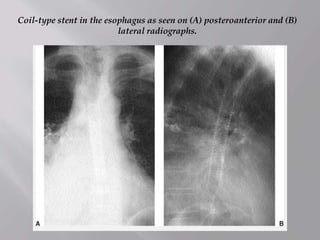

Coil-type stent in the esophagus as seen on (A) posteroanterior and (B)

lateral radiographs.